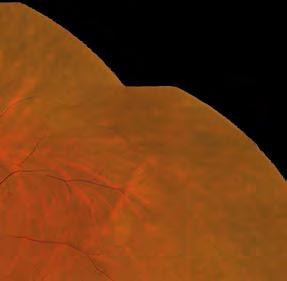

Dry eye patients at Park Vison have pre-treatment diagnostic measurements taken, including tear interferometry, tear film break-up time (TBUT), tear meniscus height (TMH), meibography, digital slit lamp images, fluorescein staining and a questionnaire on symptoms. This is not only important for clinical decision-making, but for patients to be able to see improvements.

Medmont Meridia TBUT and meibography